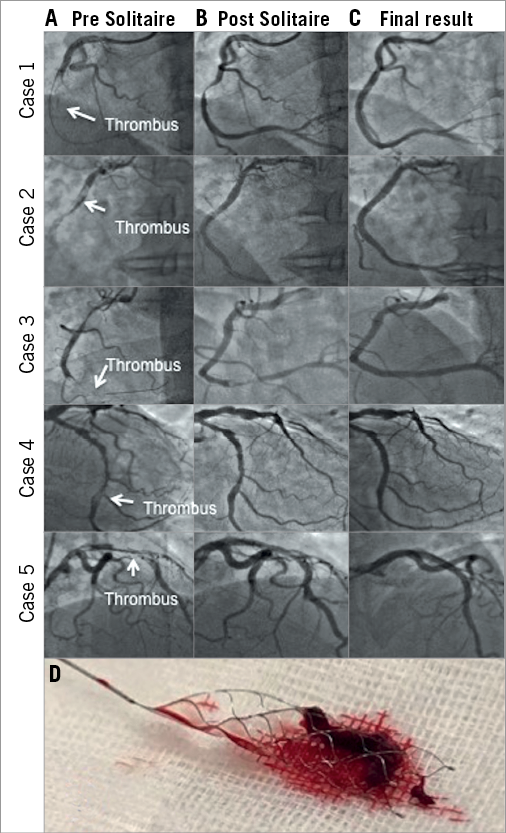

Figure 1. Five cases demonstrating reduction in thrombus load after Solitaire deployment. Column A demonstrates heavy thrombus burden in the coronary arteries of 5 patients before use of the Solitaire device. Column B demonstrates significant reduction in thrombus burden following use of the Solitaire device with improvement in distal flow. Column C demonstrates the final angiogram post stent placement at the conclusion of the procedures. Panel D shows a large organised thrombus extracted on the Solitaire device from case 2.

The Solitaire was used in a series of seven patients presenting with acute coronary syndrome with heavy thrombus burden. Prior to using the Solitaire, all seven patients received intracoronary eptifibatide and underwent aspiration thrombectomy. One was treated with the AngioJet™ Peripheral Thrombectomy System (Boston Scientific, Marlborough, MA, USA) and another returned for deferred stenting. The Solitaire was used as a last resort when established methods failed to reduce thrombus and restore blood flow. Use of the device was associated with impressive reductions of TIMI thrombus grades from 4 or 5 to 1 or 0 with improvement in TIMI flow by 1 to 2 grades as shown in Figure 1 (Moving image 3-Moving image 8).